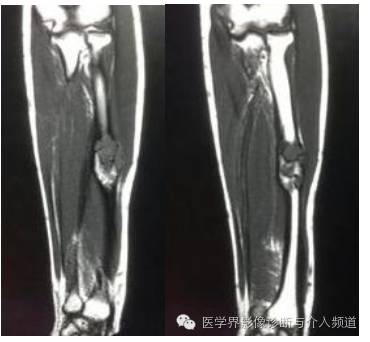

T1WI

MR:一般呈多囊状改变,37%-87.5%的病例囊内有液液平面,在扫描前保持不动10分钟较容易显示。T2WI上液平面上层一般为高信号,可能为血清液或高铁血红蛋白;下层为低信号,可能是细胞及碎裂细胞产物。